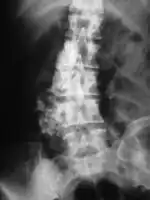

Imaging studies - including radiographs ("x-rays"), computerized tomography (CT), and magnetic resonance imaging (MRI) - are often used to make a presumptive diagnosis of chondrosarcoma.[11] However, a definitive diagnosis depends on the identification of malignant cancer cells producing cartilage in a biopsy specimen that has been examined by a pathologist. In a few cases, usually of highly anaplastic tumors, immunohistochemistry (IHC) is required.

There are no blood tests currently available to enable an oncologist to render a diagnosis of chondrosarcoma. The most characteristic imaging findings are usually obtained with CT.

Imaging